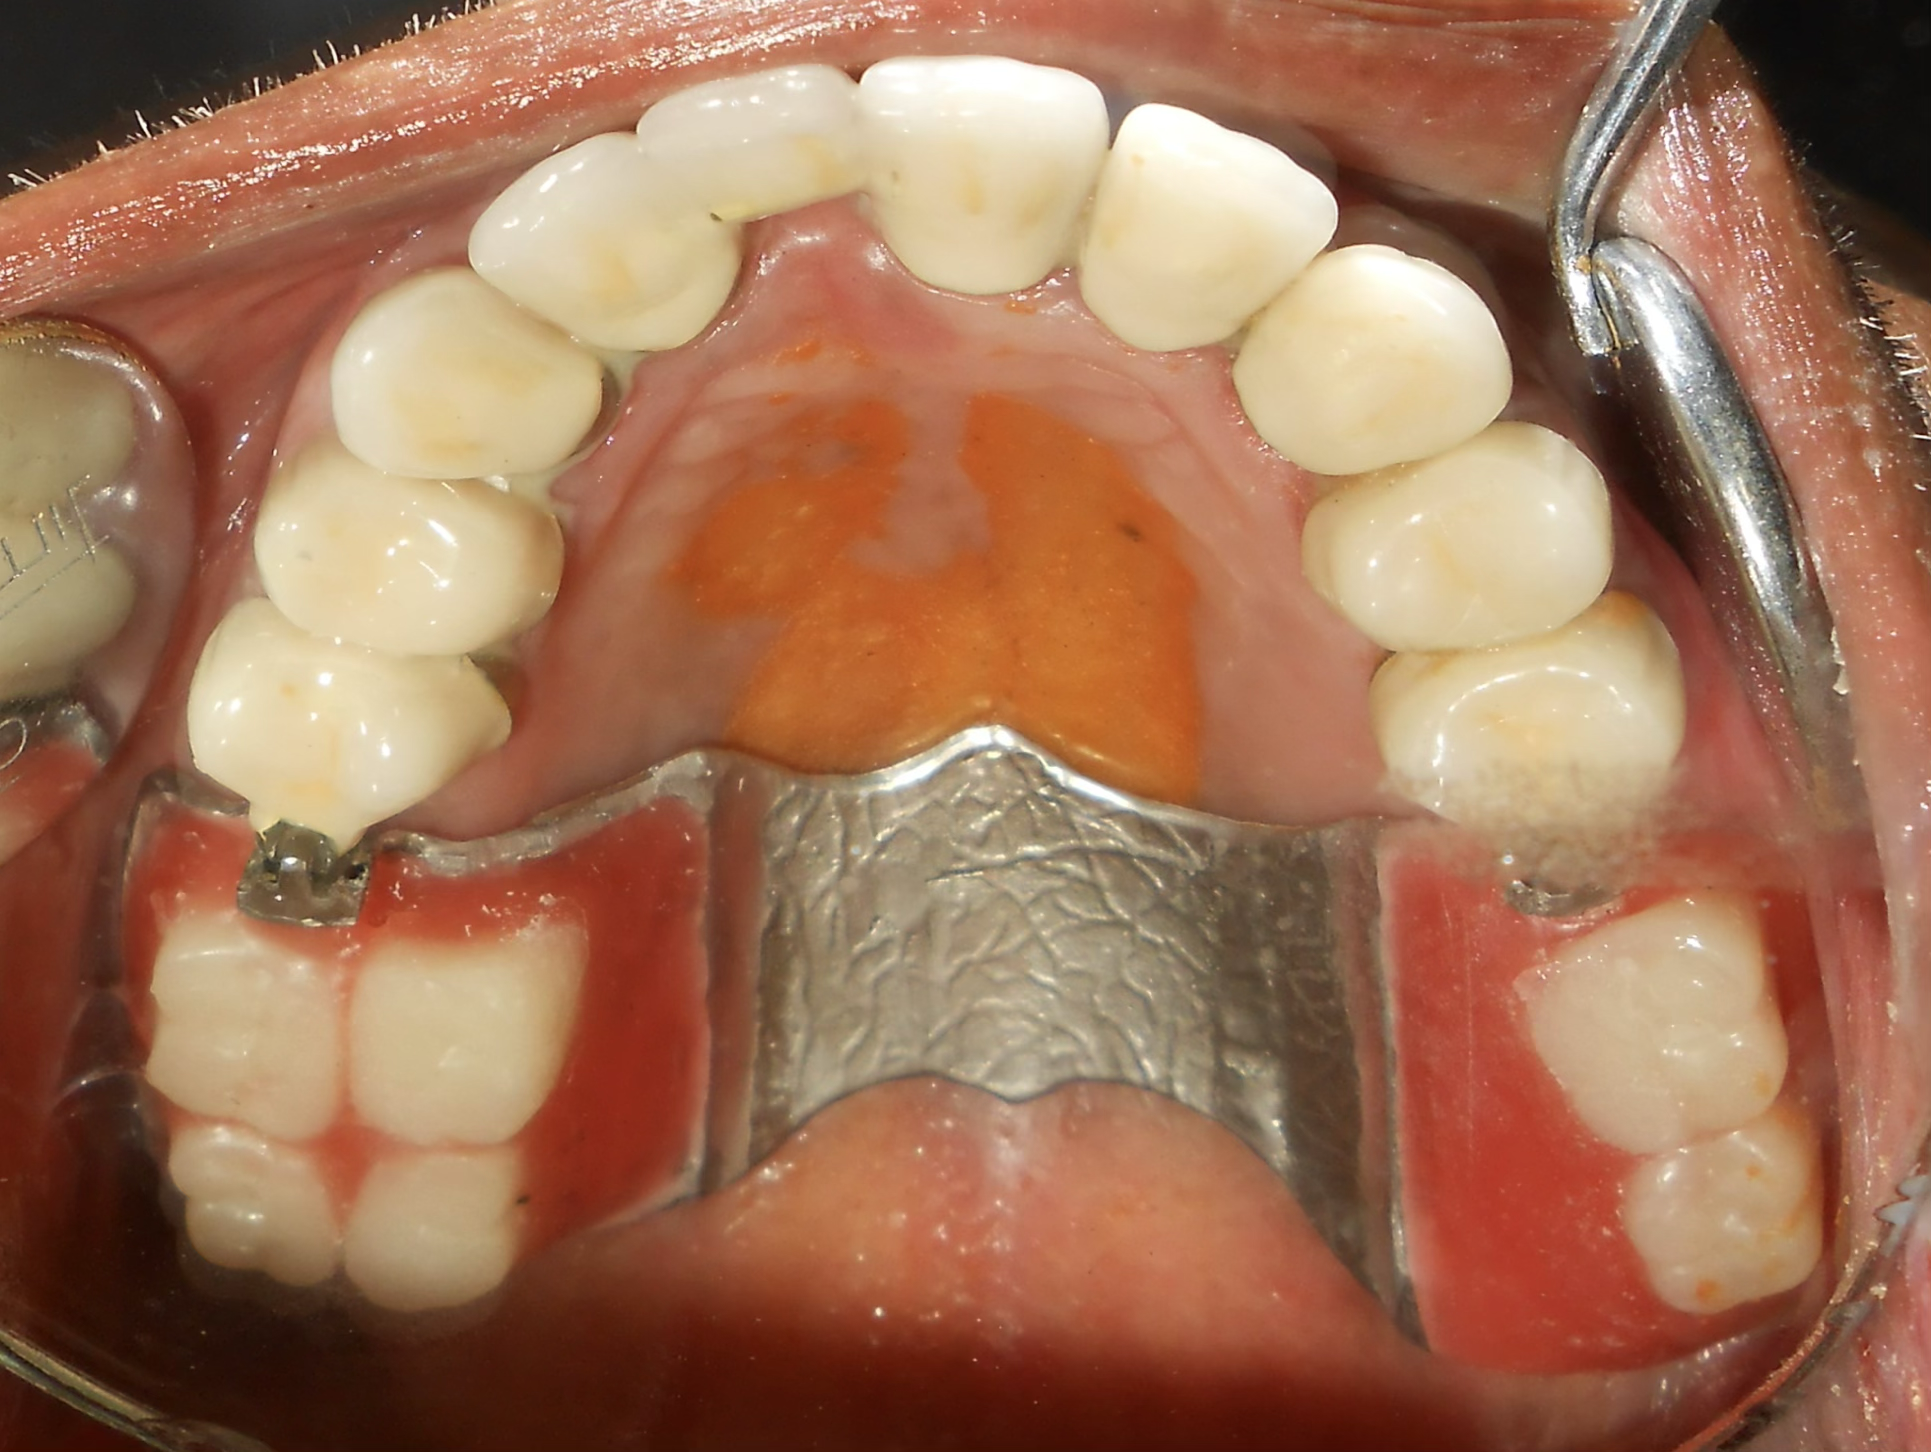

PFM crowns were fabricated and fixed for the upper remaining teeth to restore function and aesthetics.

Precision-attached metal framework fabricated and tested. Custom teeth arrangement trial to ensure optimal function and appearance.

Implants were delayed loaded after 3 months with PFM crowns. Precision-attached metal removable denture was inserted for comprehensive hemimandibulectomy rehabilitation.